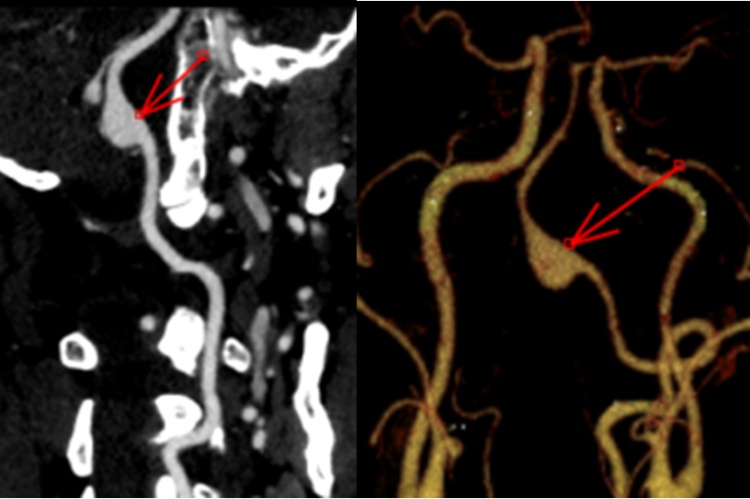

刀尖起舞,游刃有余!外四科(神经外科)成功进行高难度颅内动脉瘤血流导向栓塞装置置入术!